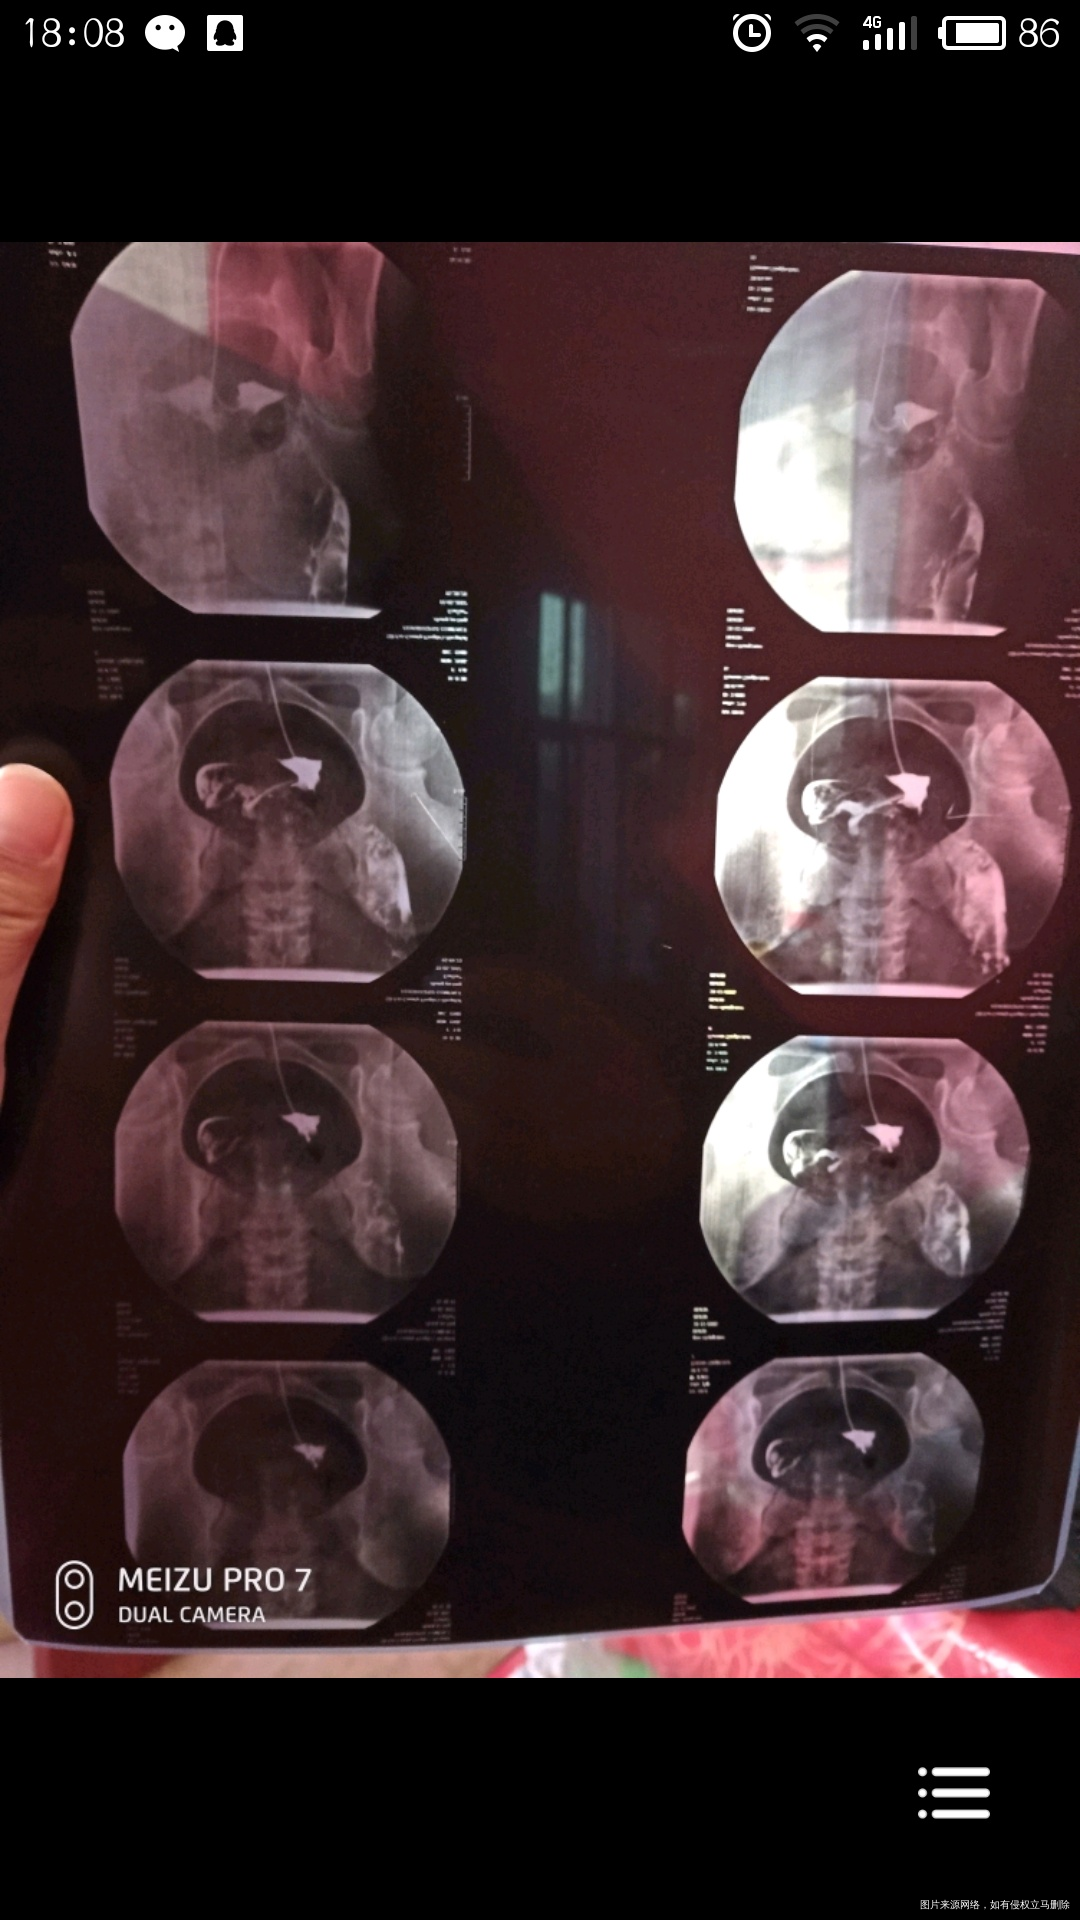

有医生告诉我,我的输卵管一侧粘连,另一测通而不畅,请问是真的嘛?有没有问题?可以要宝宝嘛?